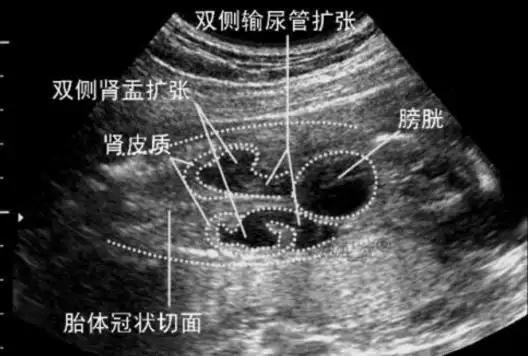

胎儿肾盂分离—如何描述和提示

胎儿肾盂分离